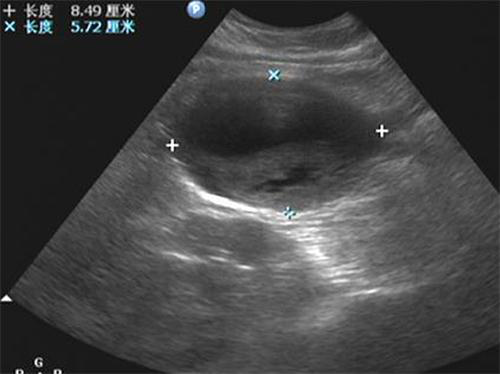

血流呈花色渦流,仔細(xì)掃查,為腹主動(dòng)脈的局部膨大,動(dòng)脈管壁完整,腔內(nèi)低回 聲考慮為血栓形成,超聲提示:真性動(dòng)脈瘤伴血栓形成。